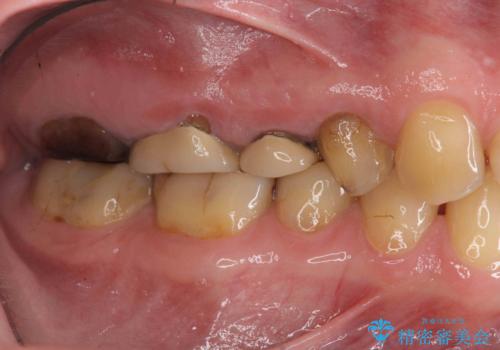

- 近医で「根尖の病変が大きく、残すことができない、歯を抜くしかない。」、と言われ歯を抜く以外の手段がないかを相談しに来院されました。

検査の結果、根管・クリアランス・虫歯といった複合的な問題が認められ、以下のような治療計画を進めることとしました。